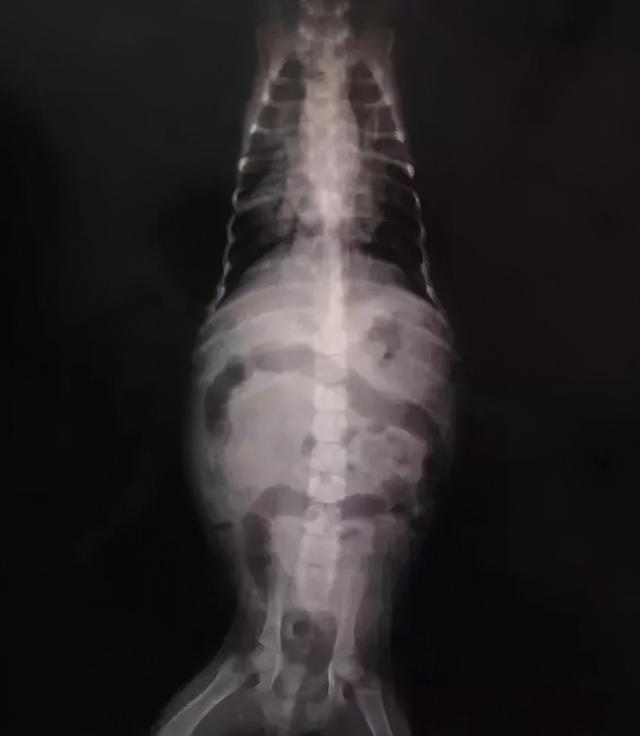

早上起来就又抱去医院,拍了片子之后发现是大叶性肺炎 犬瘟,犬瘟,根本不是细小。

贝儿的感染很严重,肠胃里全是气泡,我不懂这些,医生说有气泡是很严重的,贝儿的气泡都能看清肠子的轮廓了。

贝儿的肺部感染面积较大,能看见的黑色阴影都是被感染的,腹部阴影都是气泡,于是开始漫长的输液之旅。